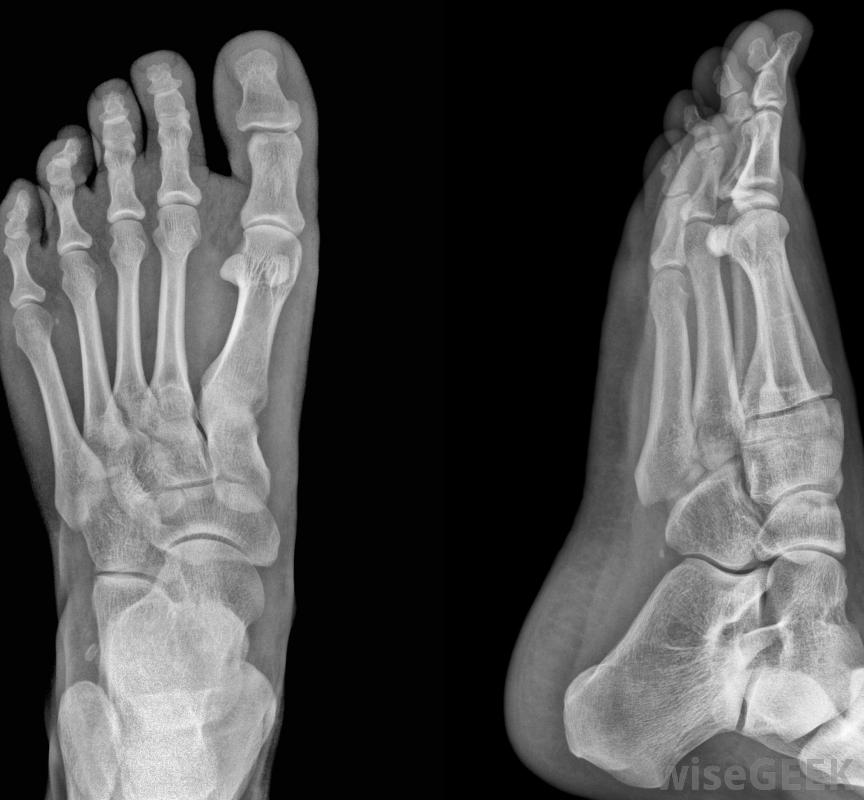

有哪些不同類型的囊腫手術(Different Types of Bunion Surgery)?

bunion手術有很多種。事實上,據估計有100多種。其中一些手術是為了去除骨頭,而另一些則是用來重新排列組織。沒有一種手術在所有情況下都能起到最好的效果。有些外科醫生對同一個人的腳進行不止一種手術根據患者的特殊情況,可以使用x光片檢查囊腫,外科醫生可能會發現有必要切除從腳部側面凸出的骨塊。這種手術被稱為束膜切除術,它可以去除隆起部分,但不能固定患者的大腳趾的位置。有時,外科醫生會從患者的大腳趾上取下整塊骨頭。這種手術被稱為截骨術,用于矯正患者的大腳趾或大腳。在這種情況下,外科醫生可能會使用特殊的裝置,比如螺絲釘或金屬絲,為了在愈合過程中保持骨骼的穩定。穿高跟鞋可能會導致發炎有時外科醫生認為在布尼昂手術中需要重新調整患者大腳趾周圍的韌帶,這種手術是為了調整患者大腳趾關節周圍的韌帶,這些韌帶要么變得比正常人松,要么比正常人更緊當這種情況發生時,患者的大腳趾會錯位,向患者其他腳趾的方向移動。重新調整韌帶可以固定移位。取決于手術類型,手術后的恢復可以持續幾個月。在某些情況下,在bunion手術中,可能需要移除患者第一個跖骨末端的骨頭。跖骨是足部的長骨之一。第一個跖骨與跖趾關節相連,跖趾關節是人的大腳趾底部的關節。在取出所需數量的骨后,外科醫生隨后會重塑受影響的骨骼,包括大腳趾骨。患有束神經痛的人可以在晚上戴上特制的夾板在一些bunion手術過程中,外科醫生可能會切除患者的一部分腳趾關節,然后將剩下的部分融合在一起。在其他情況下,在受損關節處插入一個或多個人工關節。這些人工關節通常是由塑料制成的有些外科醫生必須對同一人的足部進行不止一種的手術才能治療囊腫無論病人接受哪種類型的囊腫手術,患者通常會有較長的恢復期。有些類型的囊腫手術涉及更多的人的軟組織或骨組織,需要更長的愈合時間。根據血囊炎手術的類型,患者可能需要六周的恢復時間,而其他患者則需要最多6周的恢復時間手術刀是一種小而鋒利的刀,在外科手術中用來做切口有幾十種可能的手術來移除一個囊膜炎。